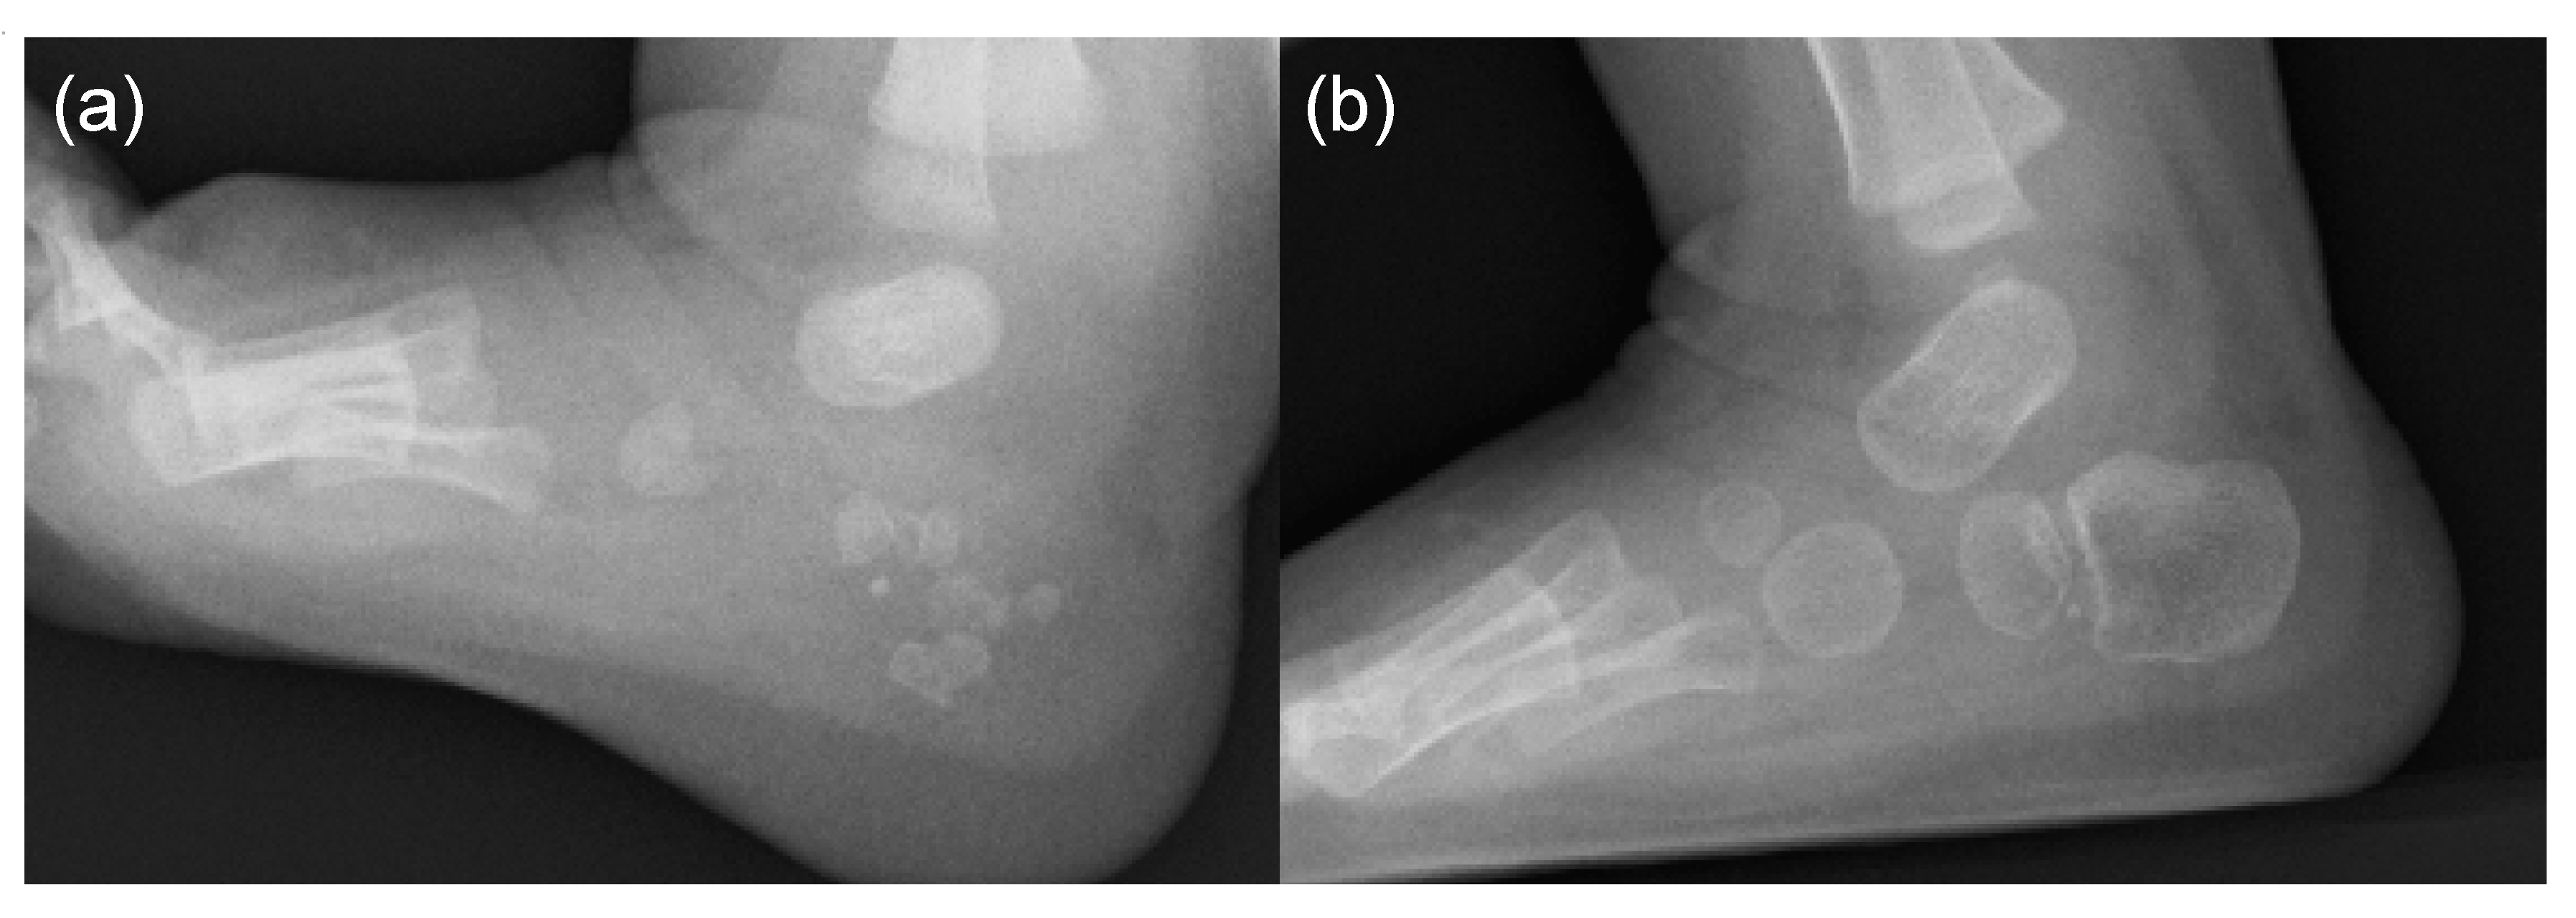

5. Skeletal Malformations

- Mishima, K.; Kitoh, H.; Katagiri, T.; Kaneko, H.; Ishiguro, N. Early clinical and radiographic characteristics in fibrodysplasia ossificans progressiva: A report of two cases. J. Bone Joint Surg. Am. 2011, 93, e52. [Google Scholar] [CrossRef]

- Hasegawa, S.; Victoria, T.; Kayserili, H.; Zackai, E.; Nishimura, G.; Haga, N.; Nakashima, Y.; Miyazaki, O.; Kitoh, H. Characteristic calcaneal ossification: An additional early radiographic finding in infants with fibrodysplasia ossificans progressiva. Pediatr. Radiol. 2016, 46, 1568–1572. [Google Scholar] [CrossRef] [PubMed]